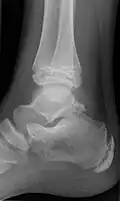

Ankle

Accessory bones of the ankle.[13]

Accessory bones at the ankle mainly include:

• Os subtibiale, with a prevalence of approximately 1%.[14] It is a secondary ossification center of the distal tibia that appears during the first year of life, and which in most people fuses with the shaft at approximately 15 years in females and approximately 17 years in males.[14]

• Os subfibulare, with a prevalence of approximately 0.2%.[15]

Os trigonum (further described below) may also be seen on an ankle X-ray.